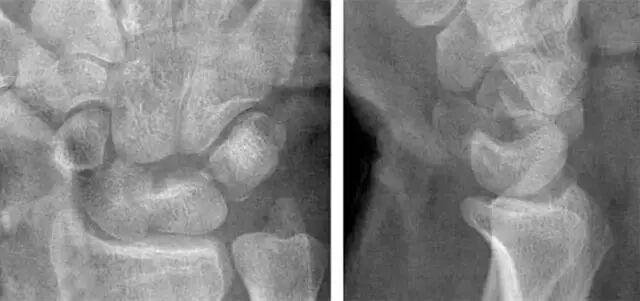

1.月骨-三角骨间隙不平行,存在重叠。

2.钩状骨和月骨也存在重叠。

3.桡骨、月骨、舟骨近极和头状骨近极平行关系存在。

4.三角骨、钩骨、头状骨远极、大多角骨和舟骨远极平行关系也存在。

5.头状骨和舟骨骨折。

诊断:经舟骨、经头状骨月骨周围骨折-脱位。